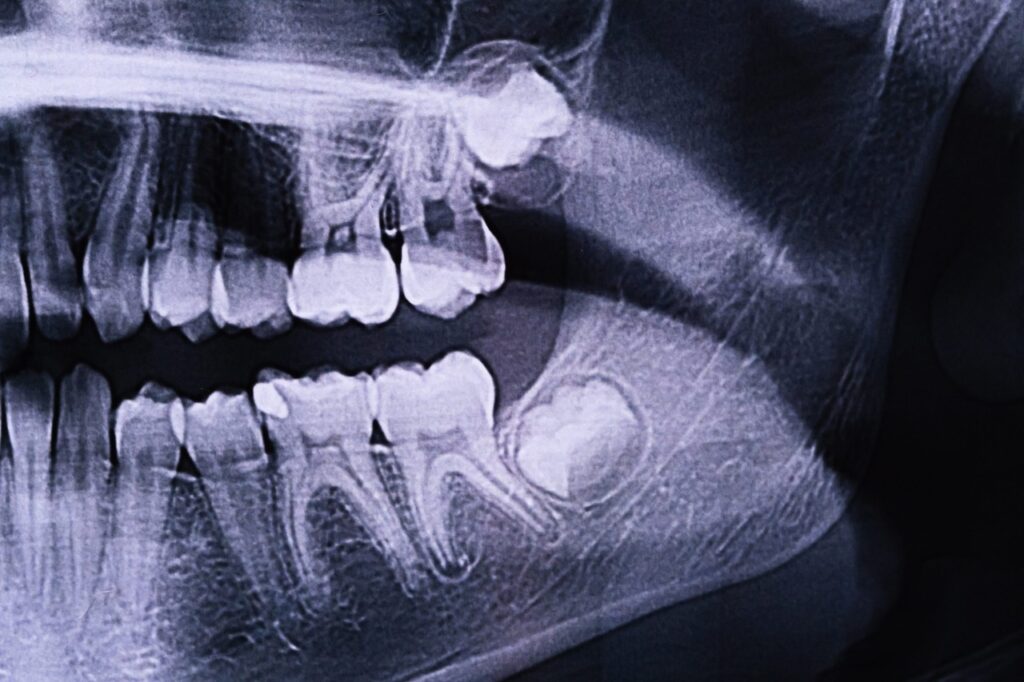

Your journey starts with a consultation. Your dentist or oral surgeon will evaluate your teeth and take X-rays to see their position. They will discuss the best course of action and provide pre-surgery instructions, which might include fasting or stopping certain medications.